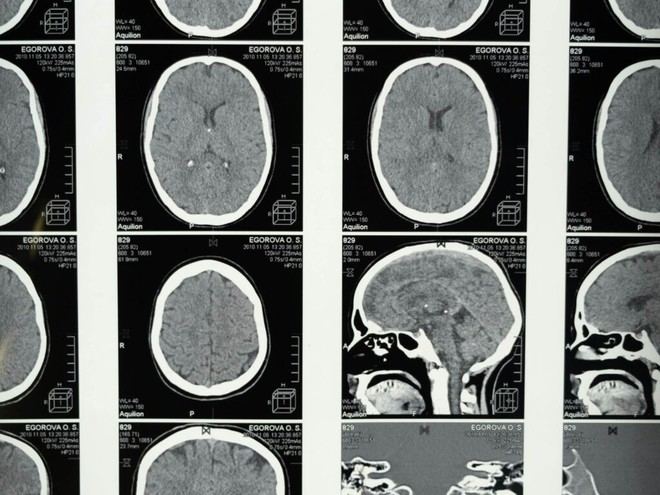

El programa destaca por su enfoque transversal, abordando desde investigaciones básicas hasta intervenciones clínicas directas. Entre las ponencias más relevantes se encuentran temas como el papel de los circuitos neurales en la Esclerosis Lateral Amiotrófica (ELA), el uso de estimulación cerebral para tratar el dolor y cómo la microbiota intestinal influye en la salud metabólica.